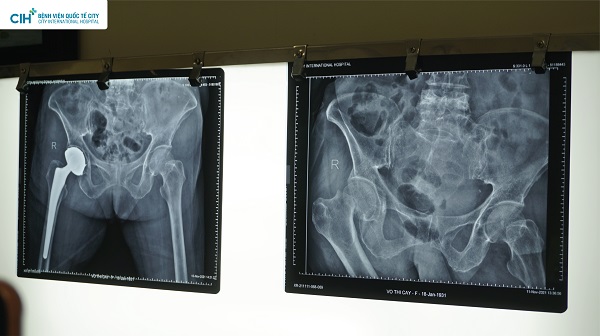

Phim trước và sau phẫu thuật thay khớp háng nhân tạo của bệnh nhân Võ Thị C

Bệnh nhân Võ Thị C, 93 tuổi, ở quận 8, TP.HCM nhập viện tại khoa cấp cứu Bệnh viện Quốc tế City khuya ngày 10/11/2021 trong tình trạng hoảng loạn sau té ngã, đau đớn, tăng huyết áp. Qua chẩn đoán hình ảnh, chụp MRI cộng hưởng từ, đánh giá tổng trạng của khớp háng và làm một số xét nghiệm cần thiết, bác sĩ kết luận bệnh nhân bị gãy kín cổ xương đùi phải (S79), loãng xương.

TS.BS. Phạm Chí Lăng, trưởng khoa Chấn Thương Chỉnh Hình Bệnh viện Quốc tế City đã nhanh chóng khám tiền mê và tiến hành phẫu thuật thay khớp háng nhân tạo toàn phần cho bệnh nhân. Ca phẫu thuật thay khớp háng nhân tạo cho bệnh nhân C đã thành công tốt đẹp ngày 12/11/2021. Sau 4 ngày phẫu thuật, bệnh nhân đã hồi phục và sức khỏe ổn định.